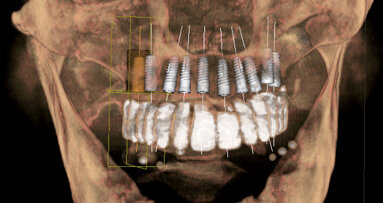

L’introduzione degli esami tridimensionali e della CBCT hanno agevolato la diagnosi e la progettazione della chirurgia atta a correggere questo inestetismo. Le tecniche digitali nell’ultimo decennio hanno rappresentato una vera e propria rivoluzione nella maggior parte delle branche odontoiatriche, Il Digital Smile Design (DSD) si è affermato come una delle più semplici e più affidabili tecnologie per diagnosticare, progettare ed eseguire trattamenti odontoiatrici in funzione dell’estetica4. La possibilità di interfacciare i dati DICOM delle CBCT, con i file STL della scannerizzazione intra-orale, con le fotografie e i video intra ed extra-orali ci consentono oggi di valutare e studiare nei minimi dettagli i casi di eruzione passiva alterata e di eseguire una chirurgia “guidata” da una mascherina chirurgica progettata in funzione dell’anatomia locale.

Una paziente di 25 anni si è presentata alla nostra attenzione per risolvere e migliorare il suo sorriso “gengivale”(Fig. 1). In prima visita lo status di rx endorali eseguite con il centratore di Rinn e la tecnica parallela confermavano la diagnosi di eruzione passiva alterata, la mancanza di “luce” negli spazi inter-prossimali e la posizione dei picchi ossei interprossimali rappresentano i segni caratteristici di questa problematica (Fig. 2). Lo studio del caso veniva completato eseguendo le fotografie, intra ed extra orali, la scannerizzazione delle arcate con uno scanner intra-orale e l’esecuzione della CBCT dell’arcata superiore (Fig. 3).

Il centro DSD di Madrid (Spagna) acquisisce tutta la documentazione per via telematica e dopo meeting su Zoom inizia a studiare il caso clinico. La prima analisi riguarda i files DICOM ove la CBCT viene analizzata in funzione dei files STL della scannerizzazione intra-orale. Ogni dente interessato dalla procedura di DSD viene misurato e così viene fatto per tutti i vari punti di riferimento (margine incisale, giunzione smalto cemento, posizione e spessore della cresta ossea, posizione e spessore della gengiva) (Fig. 4). Il progetto DSD inizia dalla valutazione iniziale delle proporzioni dei denti e delle gengive nel sorriso del paziente. La corretta dimensione dello smalto viene in questo caso derivata dalla sovrapposizione dei dati DICOM con i files della scannerizzazione intra-orale (Figg. 5a-6b).

Fig. 4_Analisi dento-parodontale.